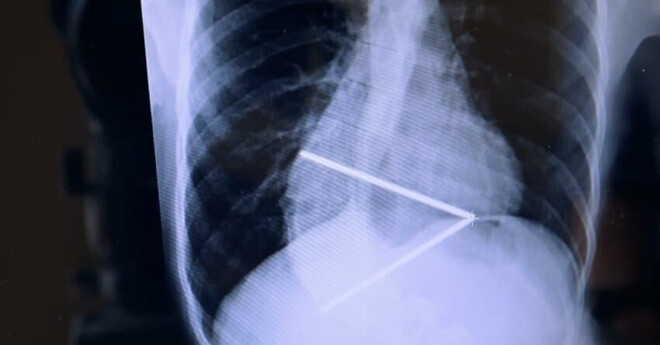

학자들이 조심스럽게 짜맞춰본 리처드의 유골은 이런 모습이었다.

일단 근거가 있었기 때문에 생겨난 루머였던것이다...

그런데, 도대체 어떻게 이리 척추가 심하게 휜 사람이 전쟁터에서 말을 타고 싸울 수 있었을까?